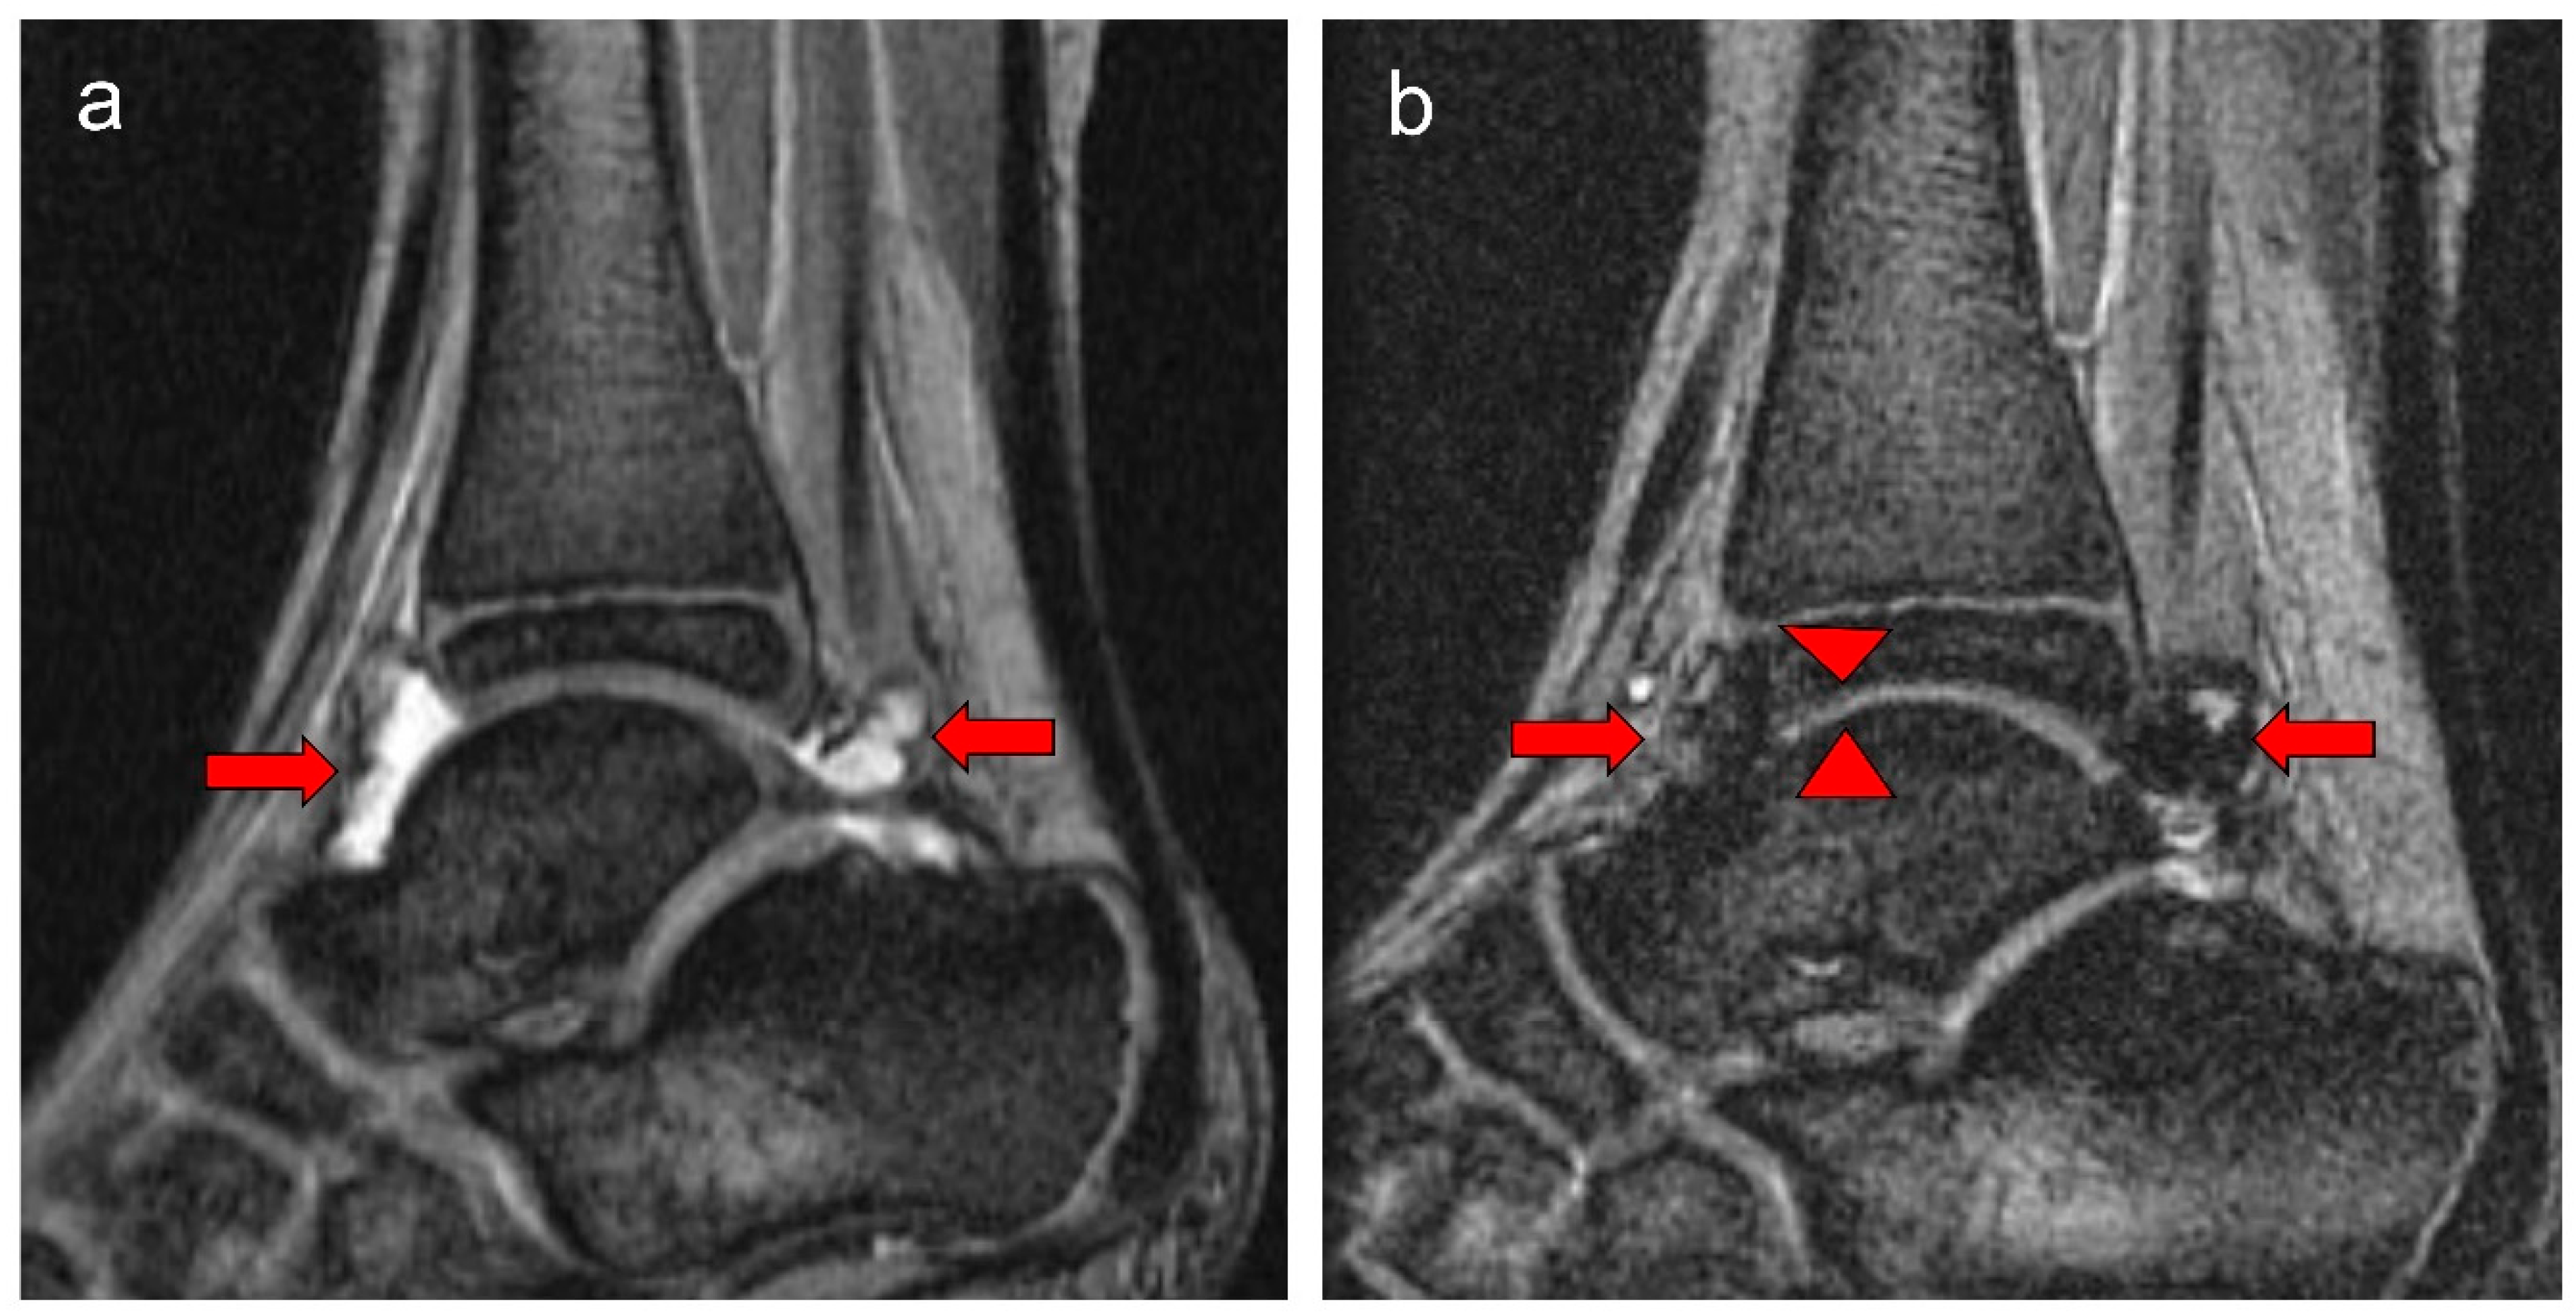

Figure 2.

Eight-year-old boy (at baseline MRI) with severe hemophilia A, and history of 9 prior left ankle bleeds and no inhibitory antibodies. Baseline (a) and follow-up (b) MR images show reversible soft tissue changes (effusion/hemarthrosis) and irreversible osteochondral change (cartilage loss) of the ankle. (a) The baseline sagittal multiplanar gradient-recalled (MPGR) MR image of his ankle shows moderate effusion (short arrows), and mild hemosiderin deposition/synovial hypertrophy, International Prophylaxis Study Group (IPSG) MRI score = 4 (effusion/hemarthrosis = 2, synovial hypertrophy = 1, hemosiderin deposition = 1). (b) The corresponding follow-up MRI shows slight increase in hemosiderin deposition (arrows) compared with the baseline MRI superposed to minimal effusion. It also demonstrates minimal focal loss in cartilage height anteriorly at the tibiotalar joint level (arrowheads). IPSG MRI score = 8; soft tissue domain = 7; osteochondral domain = 1 (effusion/hemarthrosis = 1, synovial hypertrophy = 3, hemosiderin deposition = 3, cartilage loss = 1).